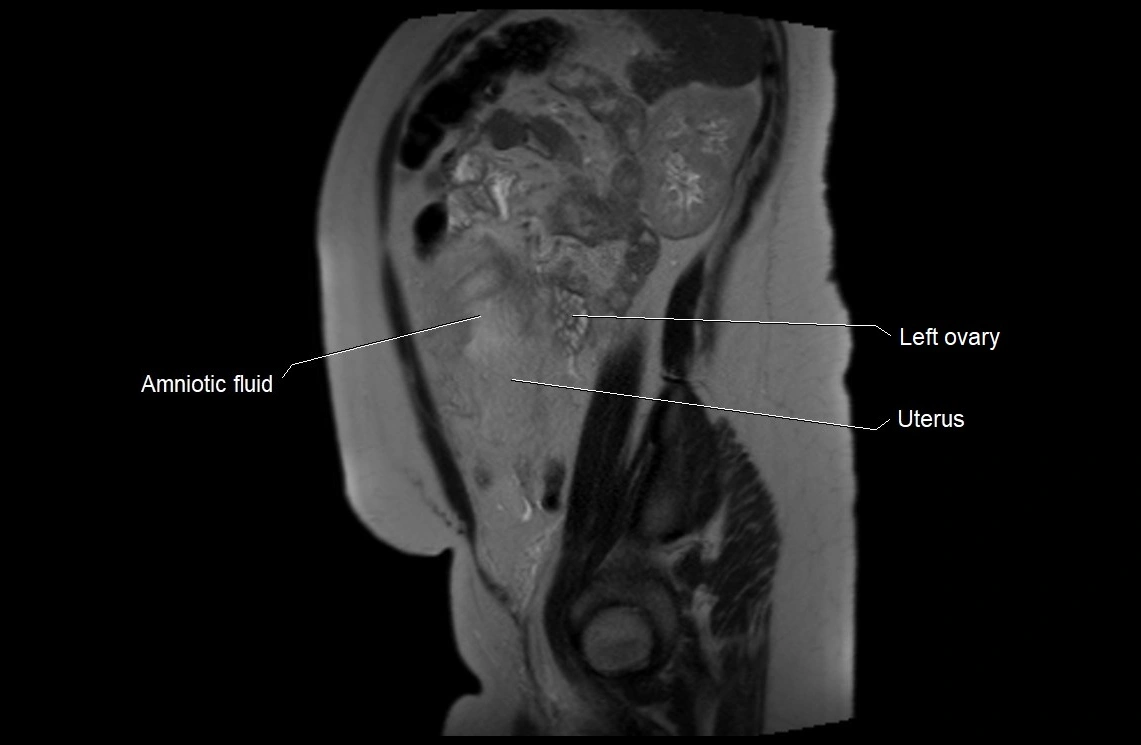

Relations

• Enclosed within the amniotic sac, bounded by the amnion and chorion

• Surrounds and cushions the developing fetus

• In continuity with maternal circulation through placental and transmembrane exchanges

MRI Appearance

T2 HASTE (T2 GRE):

• Amniotic fluid shows very bright hyperintense signal

• Provides natural contrast against fetus and placenta

MRI image

image